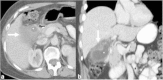

Malignancies of the biliary tract include cholangiocarcinoma, gallbladder cancers and carcinoma of the ampulla of Vater. Biliary tract adenocarcinomas are the second most common primary hepatobiliary cancer. Due to their slow growing nature, non-specific and late symptomatology, these malignancies are often diagnosed in advanced stages with poor prognosis. Apart from incidental discovery of gall bladder carcinoma upon cholecystectomy, early stage biliary tract cancers are now detected with computed tomography (CT) and magnetic resonance imaging (MRI) with magnetic resonance cholangiopancreatography (MRCP). Accurate characterization and staging of these indolent cancers will determine outcome as majority of the patients' are inoperable at the time of presentation. Ultrasound is useful for initial evaluation of the biliary tract and gallbladder masses and in determining the next suitable modality for further evaluation. Multimodality imaging plays an integral role in the management of the biliary tract malignancies. The imaging techniques most useful are MRI with MRCP, endoscopic retrograde cholangiopancreatography (ERCP), endoscopic ultrasound (EUS) and positron emission tomography (PET). In this review we will discuss epidemiology and the role of imaging in detection, characterization and management of the biliary tract malignancies under the three broad categories of cholangiocarcinomas (intra- and extrahepatic), gallbladder cancers and ampullary carcinomas.